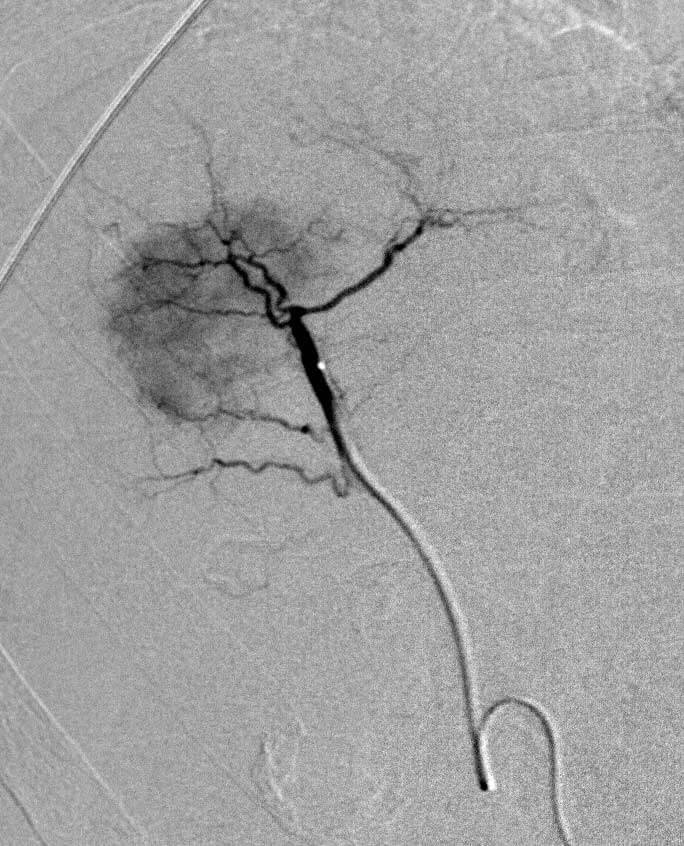

Radioembolization is a procedure used in the treatment of both primary tumors of the liver (such as hepatocellular carcinoma and cholangiocarcinoma) and metastatic disease involving the liver in diseases such as colon cancer, neuroendocrine tumors, breast cancer, etc. The procedure involves the administration of small radioactive microspheres (containing yttrium-90) directly into the blood vessels bringing blood into the tumors in the liver in order to expose those tumors to radiation.

Chemoembolization

Chemoembolization is performed by IR to treat primary tumors of the liver (such as hepatocellular carcinoma) and metastatic disease involving the liver (such as colon cancer, neuroendocrine tumor, thyroid cancer, etc.). The procedure involves the administration of small microspheres and chemotherapy directly into the blood vessels bringing blood into the tumors in the liver. These beads allow for the slow release of chemotherapy into the tumor for prolonged treatment.